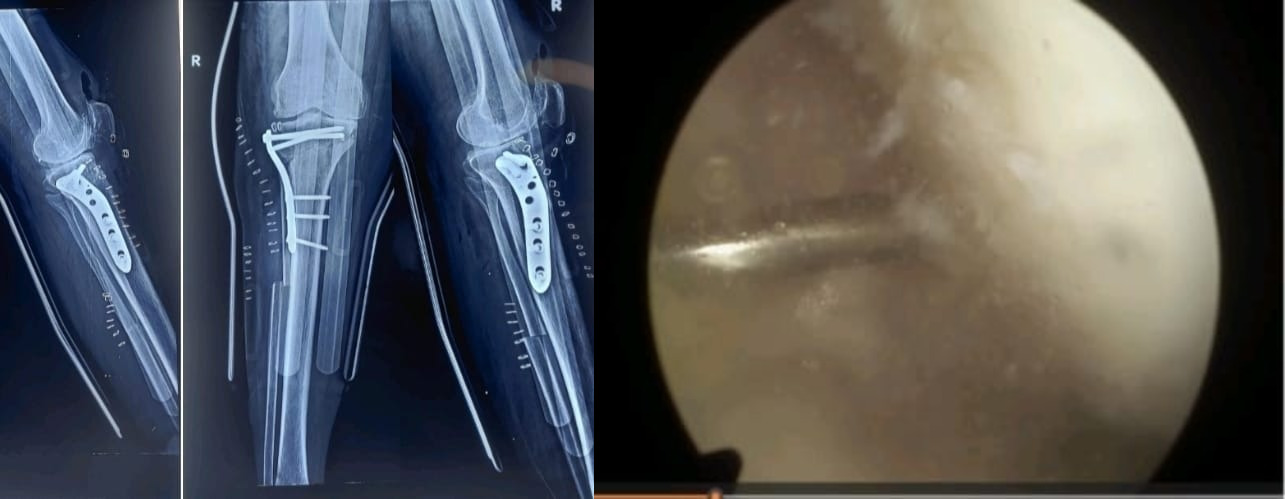

लखनऊ। उत्तर प्रदेश में पहली बार, संजय गांधी पीजीआई लखनऊ के आर्थोपेडिक विभाग ने एक अत्याधुनिक संयुक्त घुटना सर्जरी को सफलतापूर्वक अंजाम दिया है। इस अभिनव प्रक्रिया में आर्थ्रोस्कोपिक माइक्रोफ्रैक्चर और हाइब्रिड हाई टिबियल ऑस्टियोटॉमी (HTO) को एक ही ऑपरेशन में किया गया। यह सर्जरी 46 वर्षीय महिला मरीज पर की गई, जो गंभीर ऑस्टियोआर्थराइटिस और अधिक वेरस विकृति से वर्षों से पीड़ित थीं।

सर्जरी के पहले चरण में आर्थ्रोस्कोपिक माइक्रोफ्रैक्चर किया गया। इस कम इनवेसिव तकनीक में आर्थ्रोस्कोप की सहायता से घुटने में छोटे-छोटे छिद्र बनाए गए, जो हड्डी के नीचे नए फाइब्रोकार्टिलेज बनने को उत्तेजित करते हैं। इससे जोड़ों में कुशनिंग बढ़ती है और दर्द में राहत मिलती है।

दूसरा और अधिक जटिल चरण था हाइब्रिड हाई टिबियल ऑस्टियोटॉमी (HTO)। इसमें टिबिया (पिंडली की हड्डी) को सटीक रूप से काटकर पुनः संरेखित किया गया, ताकि वजन का भार घुटने के क्षतिग्रस्त आंतरिक हिस्से से हटकर स्वस्थ बाहरी हिस्से पर शिफ्ट हो सके। इस सुधार से वेरस विकृति ठीक होती है और घुटने के प्राकृतिक जोड़ की आयु में उल्लेखनीय वृद्धि होती है।